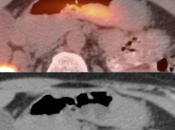

• Hiatal Hernia: Increased metabolic activity is frequently encountered within a hiatal hernia. Such uptake is nearly always physiologic or inflammatory. Malignancy, however, sometimes cannot be excluded and upper endoscopy may be required.

False Negatives:

• Lesions less than 8.0 mm: These very small lesions (primary or metastatic) may have minimal or no appreciable uptake, as they are “beneath the resolution of PET”.